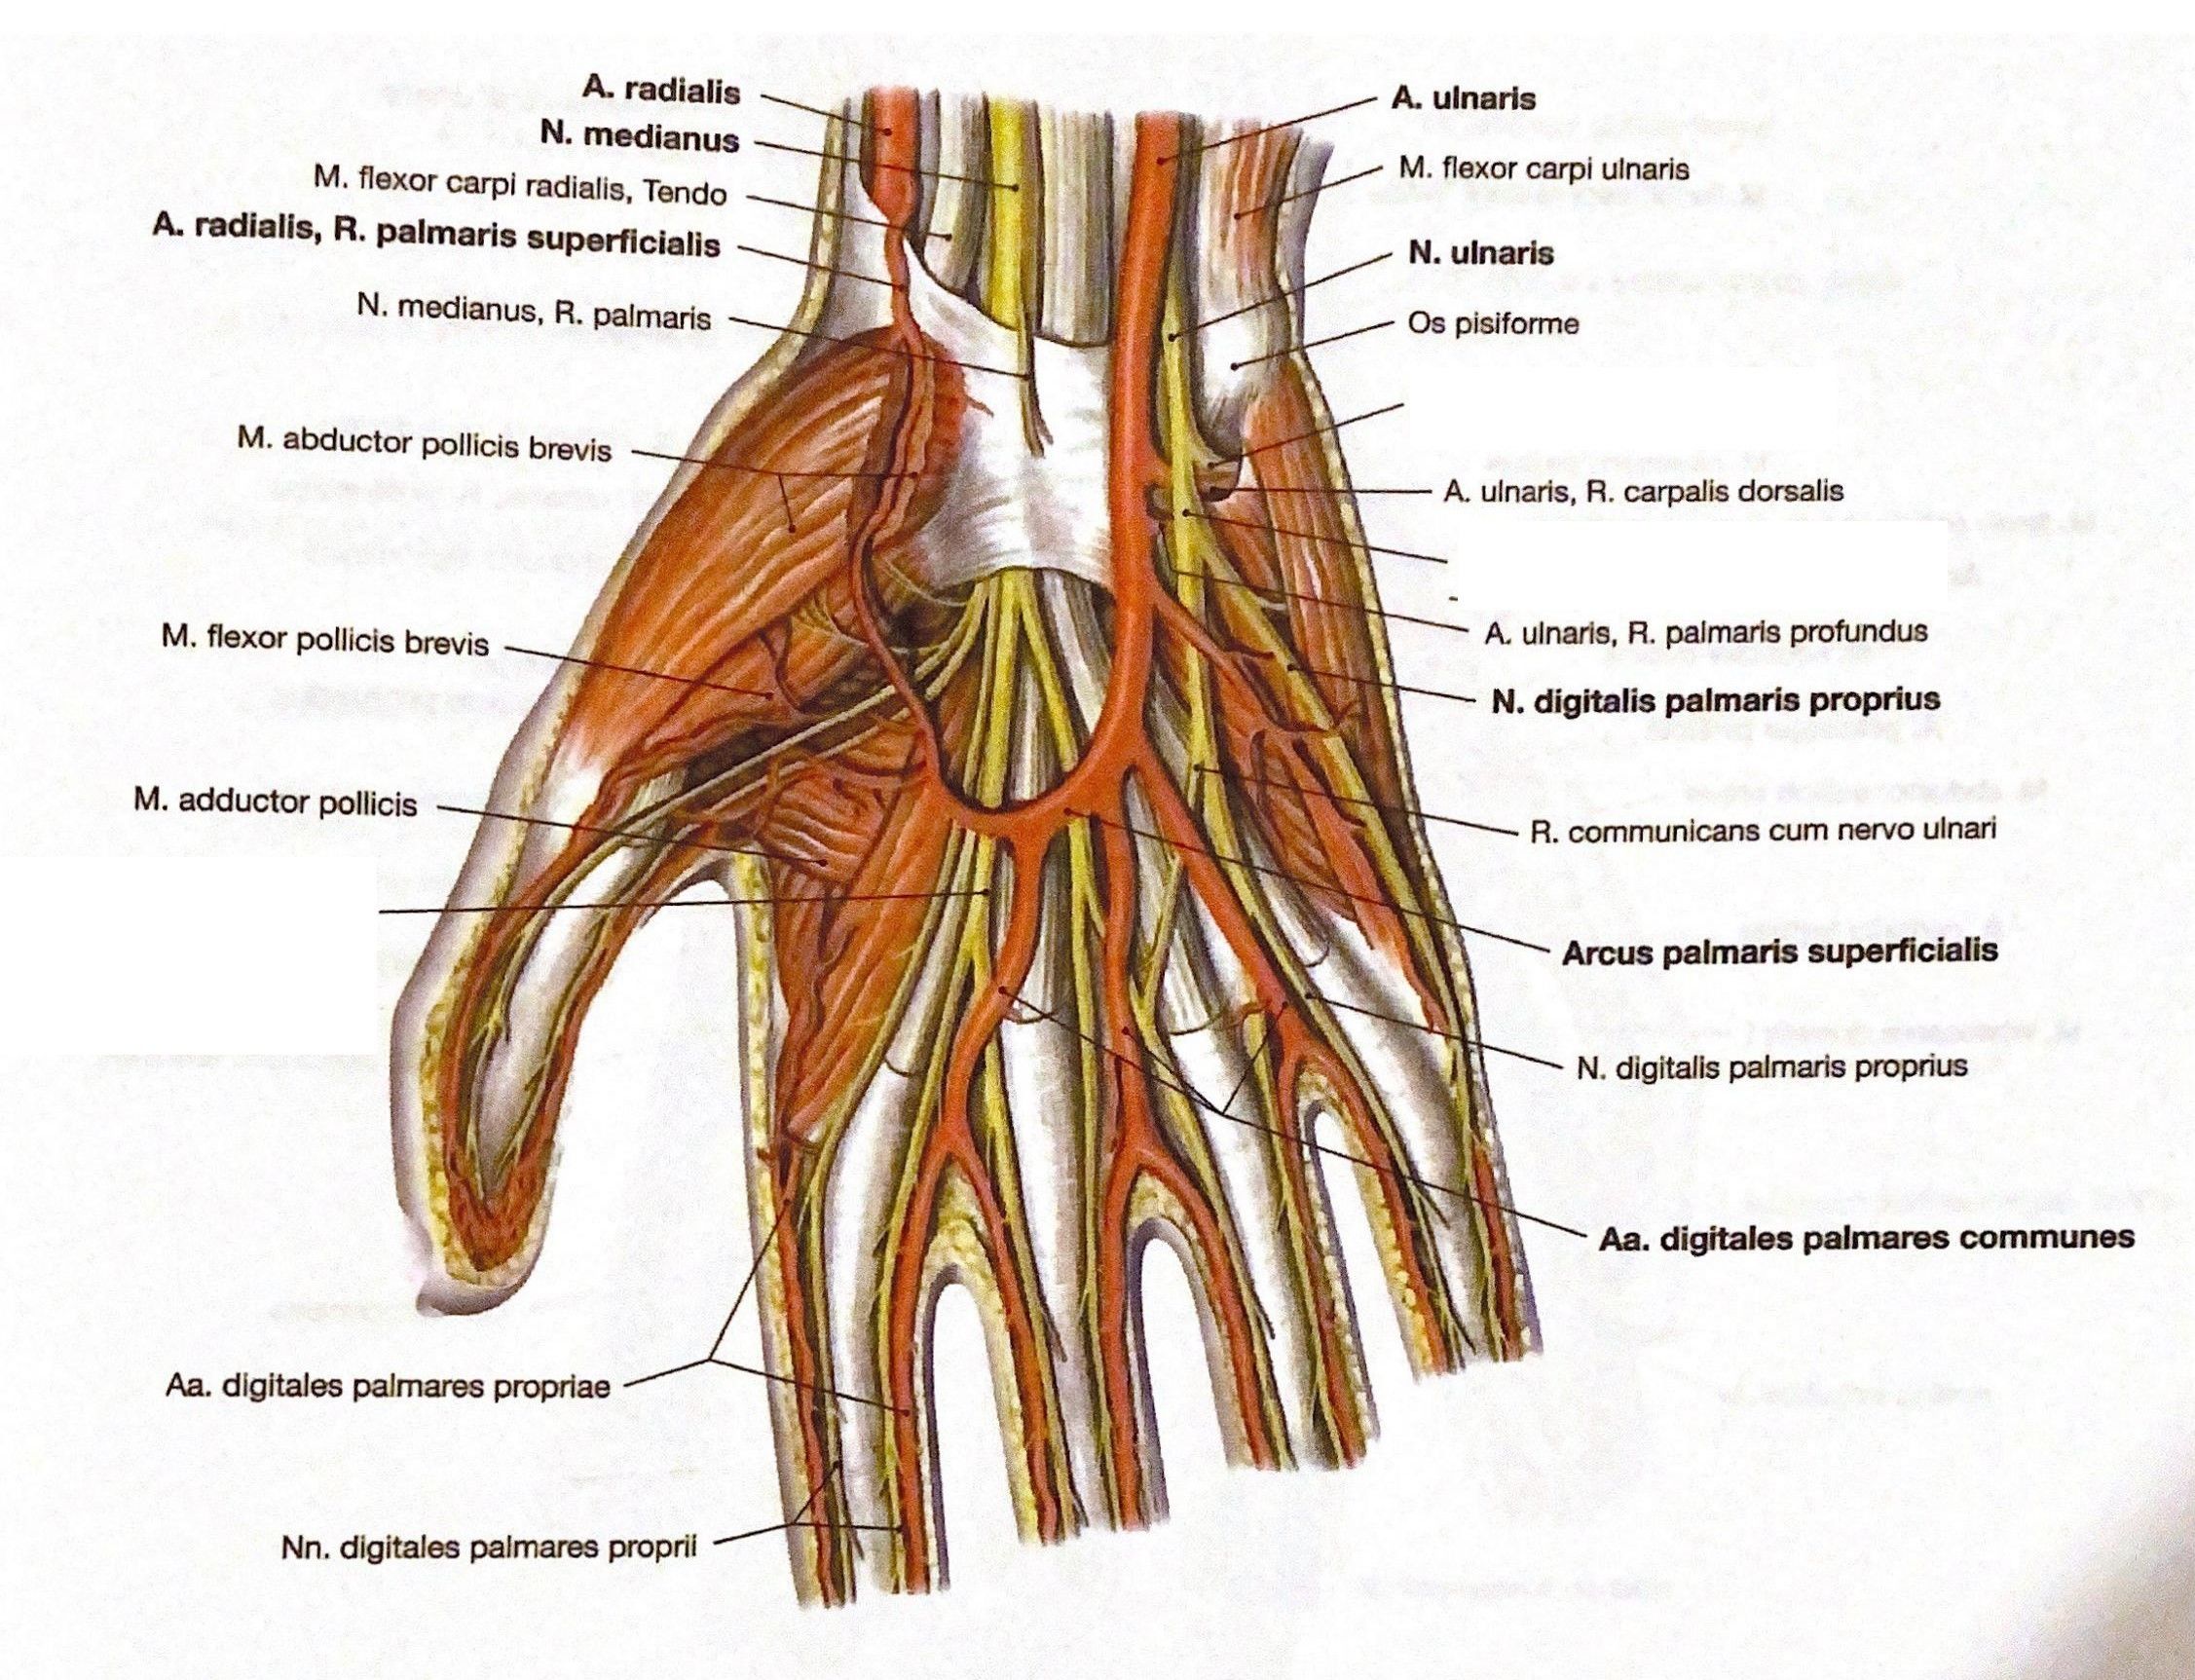

Анатомия мышцы Palmaris Longus